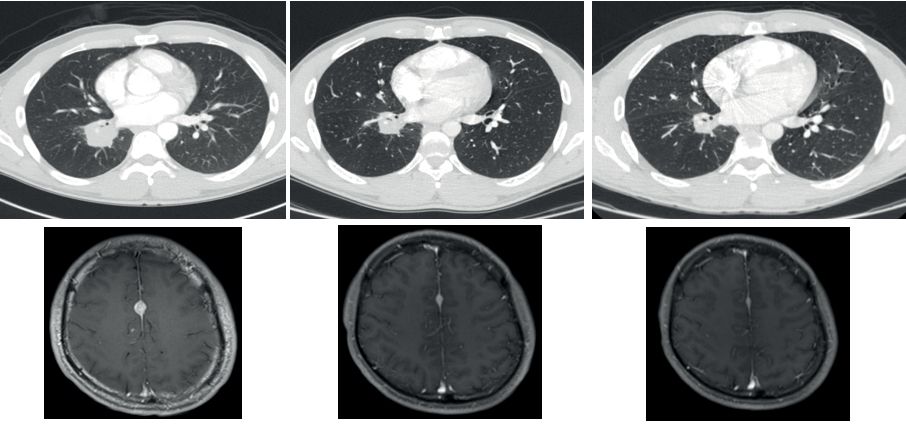

昨天关于第二代TRK靶向药物的论文刚刚发表,最初的两位耐药患者尝试新药后,肿瘤再次快速缩小。比如下面这位,用药一个月后,耐药的肿瘤就再次几乎消失!

耐药后 使用2代药一个月后

LOXO-195上个月已经被FDA批准正式开展临床试验,耐药患者有了新希望。